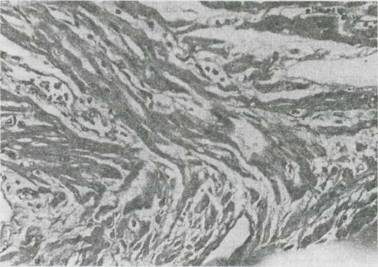

Fig. 9-13. Miocardita acuta virala la un sugar īn vārsta de 4 luni. Aspect histologic (col.HE). Se remarca edem interstitial, infiltrat inflamator īntre fibrele miocardice care sunt distorsionate, dezorganizate si si-au pierdut structura striata caracteristica.

Fig. 9-14. Miocardita acuta virala. Aspect histologic (col.HE, x 63). Infiltrat

Fig. 9-15. Miocarditaīn SIDA. Aspect histologic (col.HE, x 63) Hemoragie miocardica severa (dreapta imaginii), edem interstitial difuz, leziuni distrofice ale miocitelor.